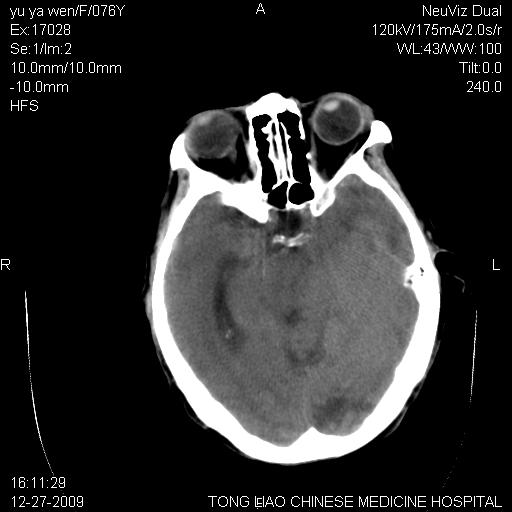

以下是引用lizhiguang在2009-12-27 19:06:00的发言:[br]脑膜瘤

以下是引用zhao_bin2008在2009-12-27 20:34:00的发言:[br]考虑脑膜瘤,伴肿瘤出血,建议增强检查

以下是引用zsl6918在2009-12-27 19:28:00的发言:[br]建议对症治疗后强化检查,考虑脑膜瘤可能性大。